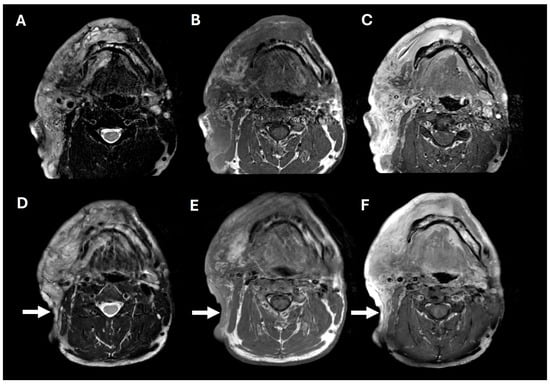

Figure 2.

Pre- and post-operative brain MRIs. Pre-operative T2, T1, and T1+contrast imaging (A–C), showing a large, T2-hyperintense, enhancing, predominantly right facial mass. Post-operative T2, T1, and T1+contrast imaging (D–F), showing posterior tumor debulking (arrows).